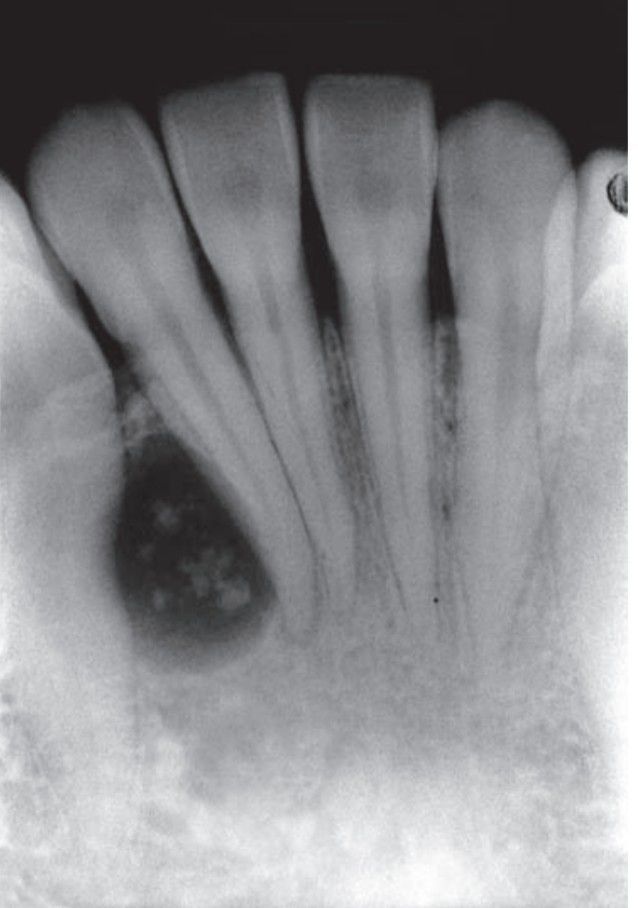

Adenomatoid odontogenic tumor

Adenomatoid odontogenic tumor with opaque foci